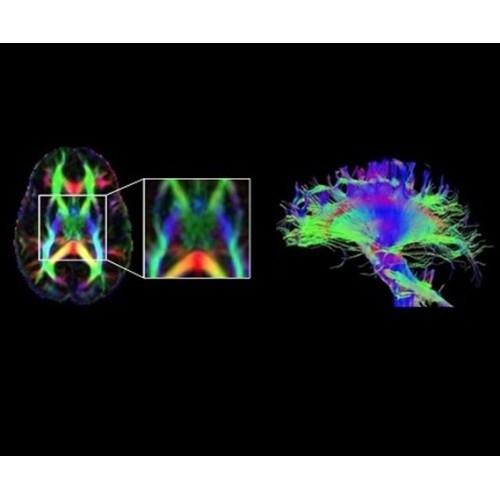

Используйте весь диагностический потенциал TOF

В систему SIGNA PET/MR встроены запатентованные детекторы кремниевого фотоумножителя (SiPM) и сверхчувствительные кристаллические сцинтилляторы на основе лютеция толщиной 25 мм. Благодаря этому обеспечивается исключительная чувствительность и возможность использования времяпролетной диагностики (TOF).

Кроме того, в результате использования технологии TOF и инновационной технологии реконструкции Q.Clear вы сможете добиться прекрасного соотношения сигнал/шум. А благодаря технологии нулевого времени эхо (ZTE) визуализировать костную структуру без ионизирующего излучения. Все эти разработки для улучшения качества сканирования и точности анализа помогут вам использовать весь потенциал ПЭТ/МРТ.